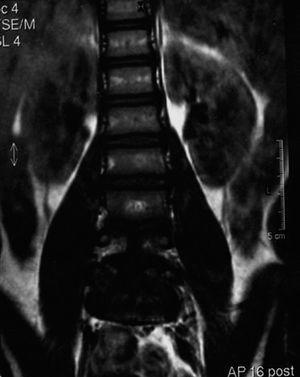

Con el diagnóstico clínico de hipertricosis localizada lumbosacra o cola de fauno y ante el alto índice de sospecha de la existencia de un disrafismo espinal oculto, se solicitó una resonancia magnética de la columna vertebral. Esta prueba de imagen puso de manifiesto la presencia de 2 vértebras (L4-L5) con morfología en mariposa (fig. 2), mostrando a nivel posterior un espolón óseo que divide el canal raquídeo en dos. Están ausentes las apófisis espinosas de dichas vértebras lumbares y de las sacras y a nivel de L3 la médula espinal se divide en 2 hemimédulas (fig. 3A). Estos hallazgos permitieron confirmar la presencia de un disrafismo oculto, compatible con una diastematomielia, apreciando una médula espinal anclada (fig. 3B).

Figura 2.RM: morfología en mariposa de las vértebras lumbares L4 y L5, mostrando un espolón óseo a dicho nivel. Se aprecia además una ausencia de las apófisis espinosas de dichas vértebras lumbares y de los elementos posteriores de las vértebras sacras.